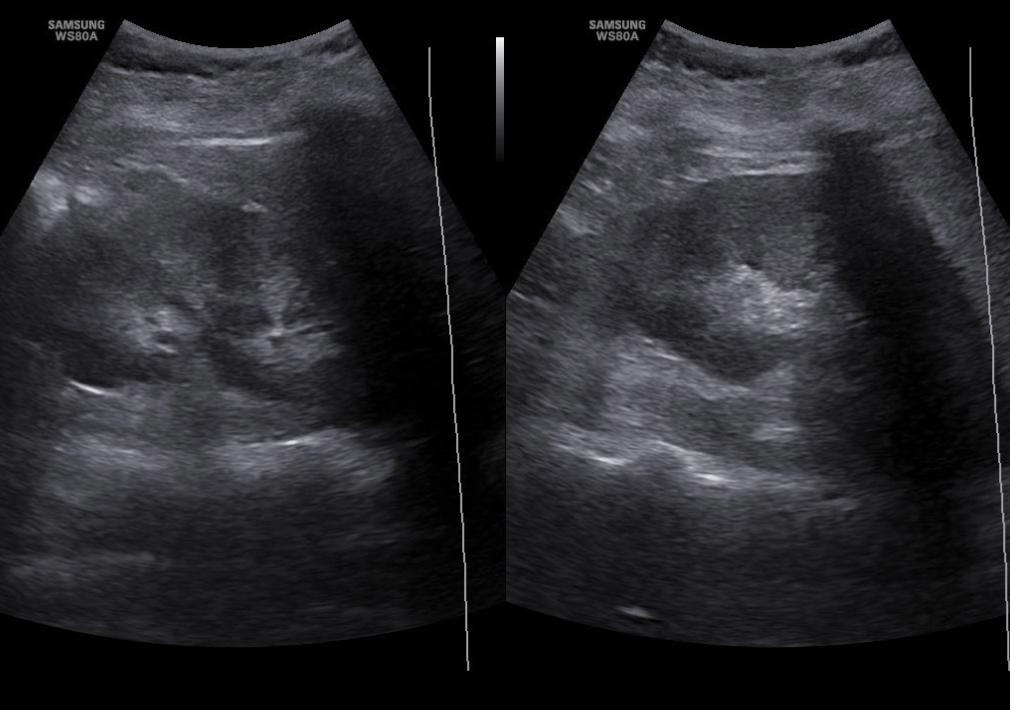

Fig. 1.

Ultrasound assessment of the right kidney. Longitudinal section of the organ on the right, transverse section on the left. On both images a hypoechoic area consistent with the dilatation of the renal pelvis is visible in the middle of the central field

Fig. 3.

Ultrasound assessment of the right kidney (longitudinal section). Visible dilatation of the pelvis and of major and minor calyces